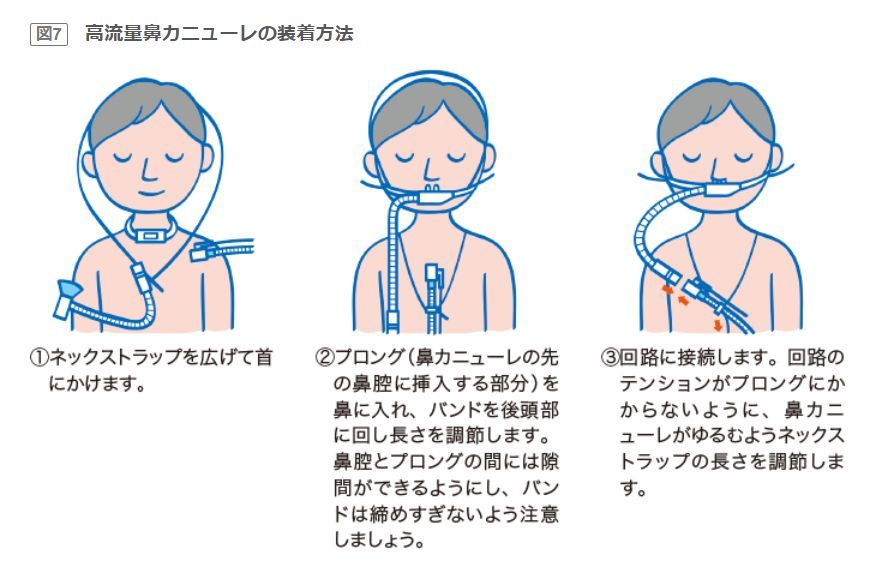

ネーザルハイフローの看護に必要な観察項目・設定の仕方を解説 一人でできるコキュトレ。

ネーザルハイフロー Nasal High Flow™ - 亀田メディカルセンター亀田総合病院 呼吸器内科 呼吸器道場。

今こそ知りたい! ハイフローセラピーのケアとアセスメント:急性期~終末期まで急性期 急性期ハイフローセラピーのアセスメントアイ・エム・アイ株式会社 IMI.Co.,Ltd。